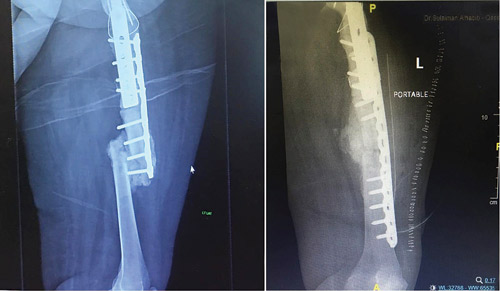

وأوضح د.عامر أن نتائج التحاليل المخبرية كشفت سبب عدم التحام العظم، إذ إن المريضة كانت تعاني من ضُعف شديد في كثافة العظام منذ الصغر، كما أوضحت فحوصات الأشعة وجود التحام خاطىء للعظام بشكل غير متساوي، بالإضافة إلى تسبب العمليات السابقة في حدوث قصر في طول الساق بمقدار 5 سم، وكذلك عدم إمكانية ثني الركبة نهائياً.

وفي ختام حديثه قال الدكتور عامر عبدالله إن جهود الفريق الطبي تكللت بالنجاح ولله الحمد، حيث أن المريضة حولت لجناح التنويم لمدة 4 أيام، وخضعت لفحص إضافي بالأشعة السينية للتأكد من نتائج العملية، وقد أظهرت الصور الشعاعية استقامة تامة في عظم الفخذ، مع إصلاح قصر الساق الناتج عن الجراحات السابقة باستعادة الطول بشكل كامل.